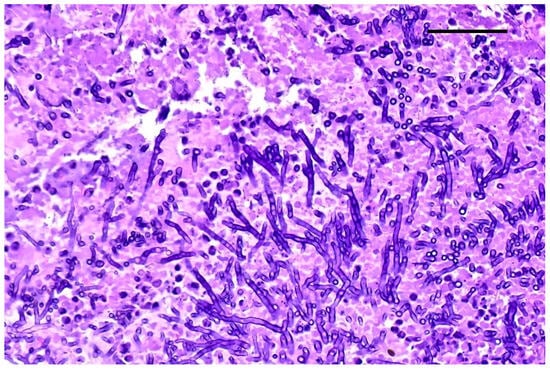

Grocott–Gomori’s methenamine silver staining revealed myriads of pseudohyphae and narrow-neck budding yeasts, suggestive of Candida albicans, mixed with the inflammatory cells described in the renal tubules (Figure 3). Multifocal areas of necrosis of lung parenchyma associated with infiltrates of pyknotic neutrophils and macrophages in the bronchiolar spaces and multifocal perivascular infiltration of lymphocytes were detected. Alveolar spaces were expanded by edema and fibrin. Numerous GMS-positive septate fungal hyphae with parallel walls and dichotomously branching, compatible with Aspergillus spp., were observed within a bronchus, mixed with necrotic debris, macrophages, and pyknotic neutrophils (Figure 4). Spleen showed white pulp hyperplasia and the presence of megakaryocytes, while the heart did not show significant findings.

Figure 3. Kidney, Grocott–Gomori’s methenamine silver stain (GMS). Numerous pseudohyphae and narrow-based budding yeasts within renal parenchyma. Original magnification 40×, scale bar: 500 µm.